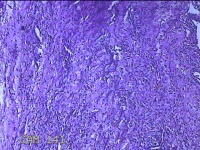

左侧卵巢囊肿⑴

性别

女

年龄

34岁

临床诊断

左侧卵巢子宫内膜异位囊肿

一般病史

下腹痛3小时入院。

标本名称

大体所见

灰白暗红色囊性肿物8x2.5x0.7cm一个,表面糜烂,部分已切开,囊内容物已流失,囊壁厚0.1cm。